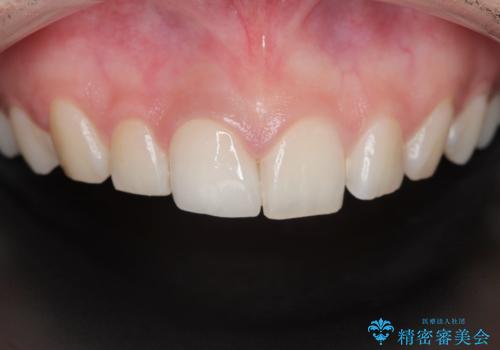

適合の良い被せ物が入り、患者様に満足していただけました。